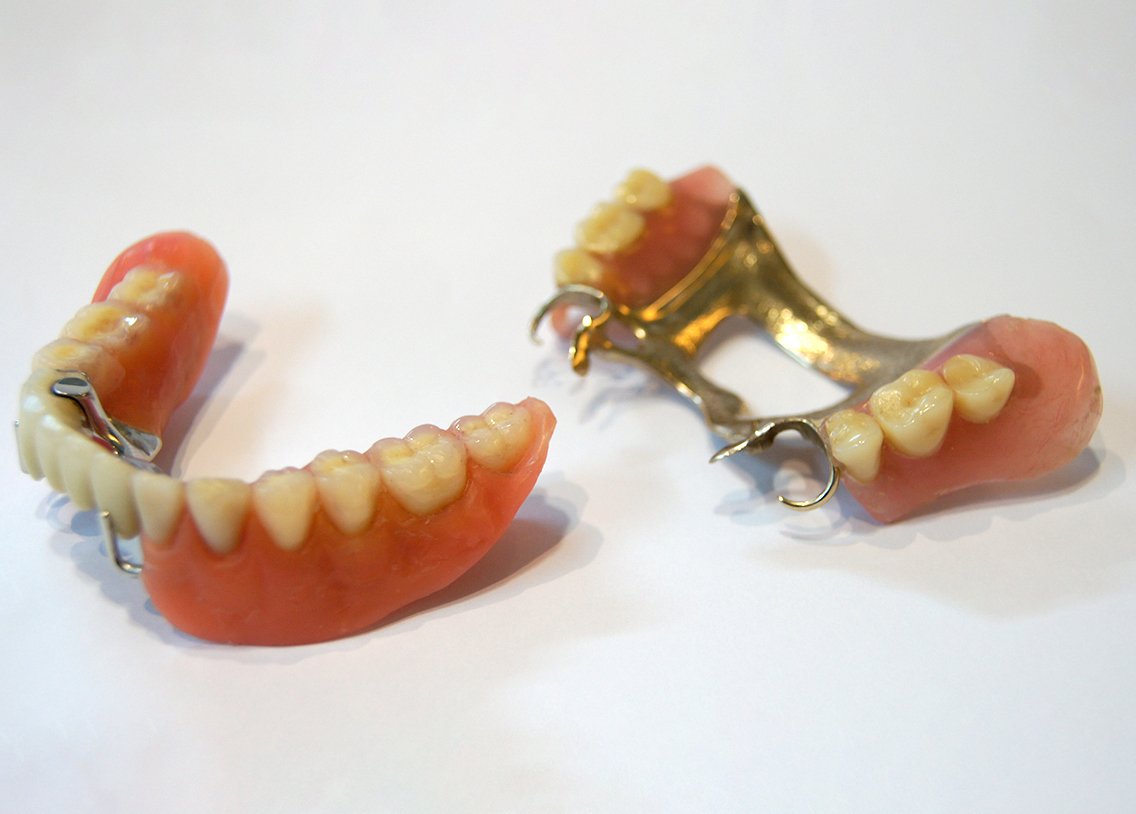

Dentures are sets of artificial teeth set into a plastic framework that rests directly on the gums.

For those who have several missing teeth and whose teeth are not strong enough to support a bridge, a partial denture is used. In this type of denture, clasps fit onto the adjoining natural teeth and the framework fits directly on the gums.

If you have lost all of the upper or lower teeth, a full denture is used. The full denture replaces all the teeth in a jaw and fits directly on the gums and the supporting bone.

It requires multiple visits (at least four visits) to complete the treatment.